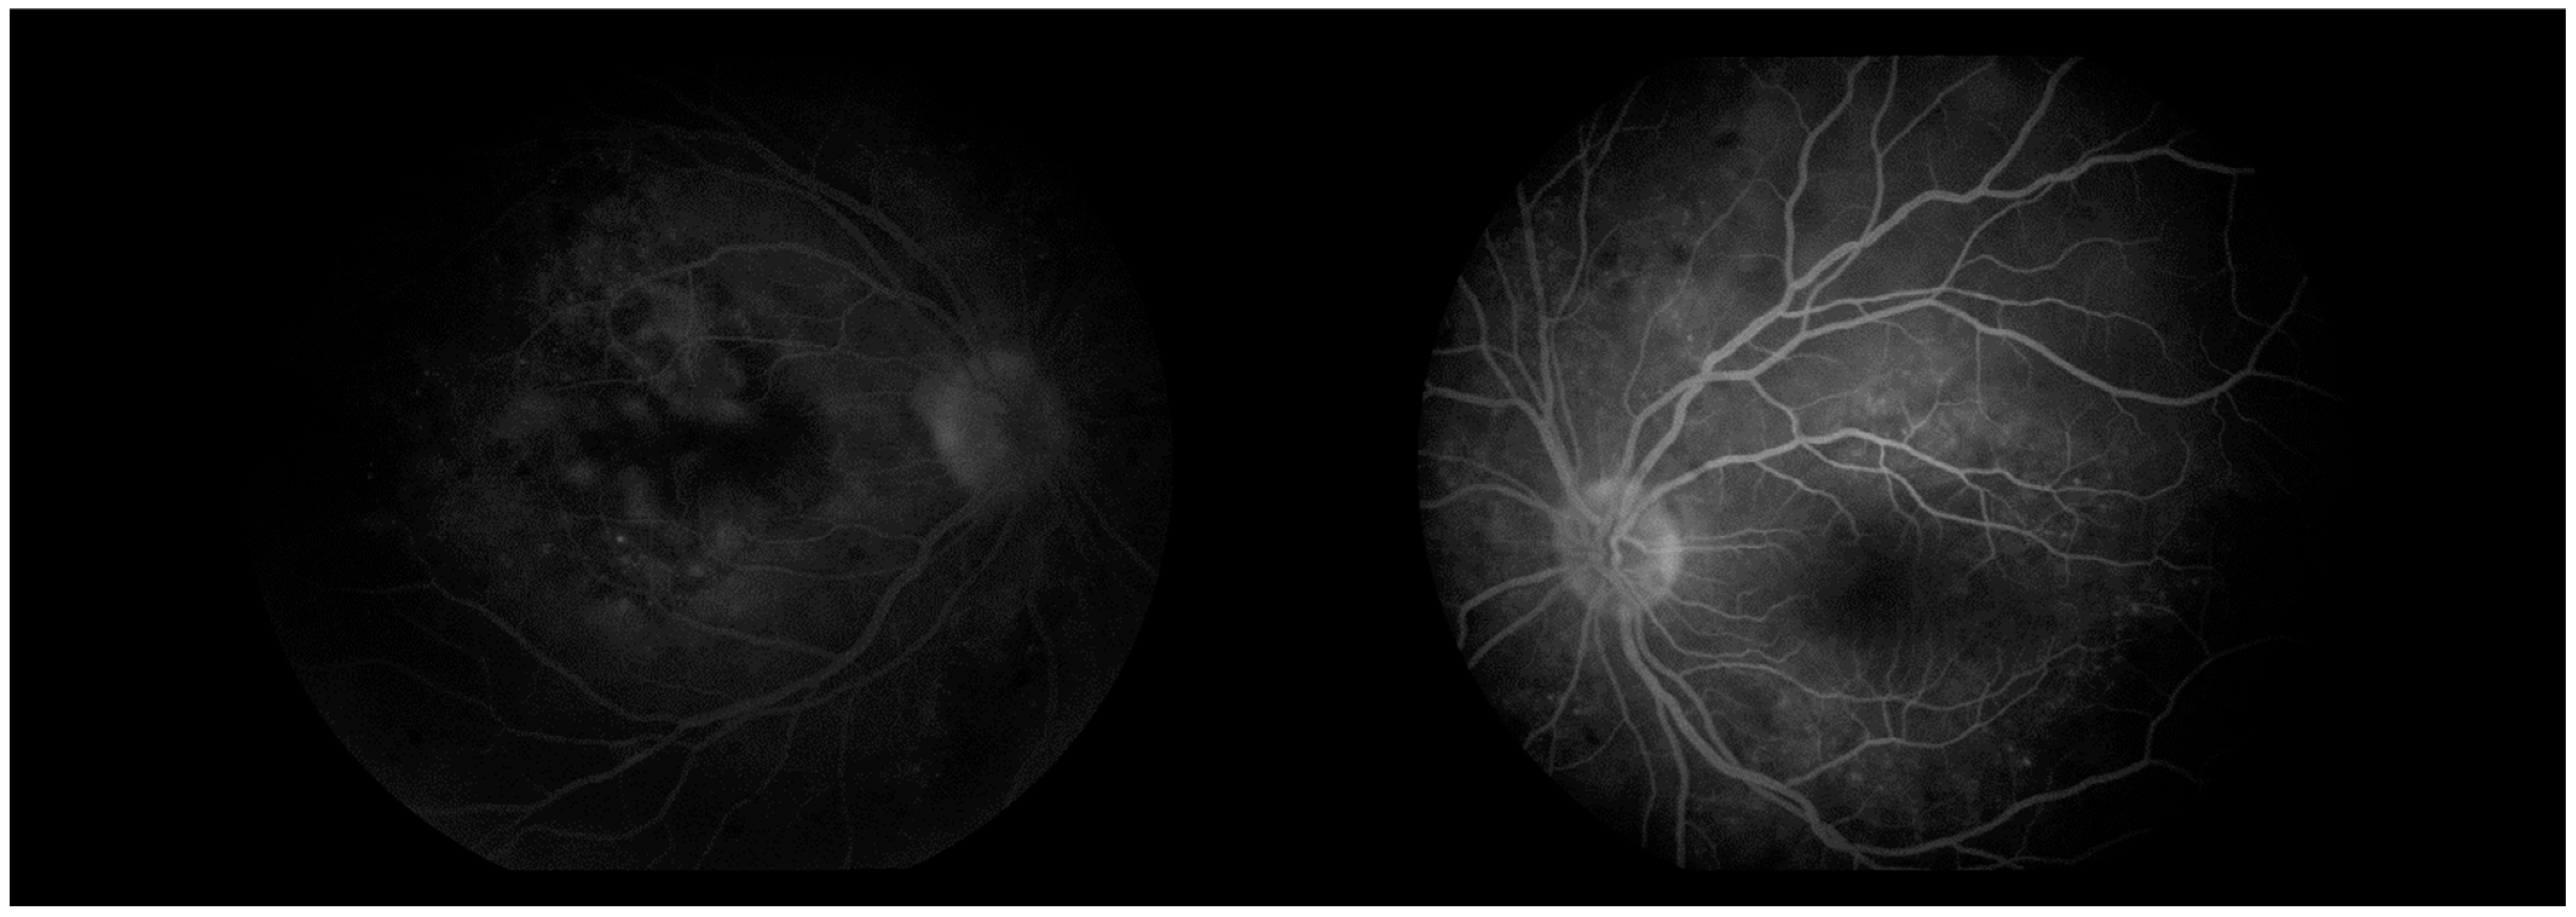

Optical coherence tomography (Zeiss Cirrus 500/5000) revealed serous fluid accumulation between the neurosensory retina and the retinal pigment epithelium, resulting in a detachment of these layers (Figure 7). In response, nonsteroidal anti-inflammatory therapy was initiated with topical Yellox drops and oral Vimovo tablets. Given the atypical presentation, a rheumatology consultation was requested, and HLA typing for B5, B27, DR1, and DR4 alleles was performed. Based on these findings, the working diagnosis was revised from primary glaucoma to a probable case of Vogt–Koyanagi–Harada syndrome.

Figure 7. OCT “HD 21 Line” analysis of both eyes showing serous retinal detachment.